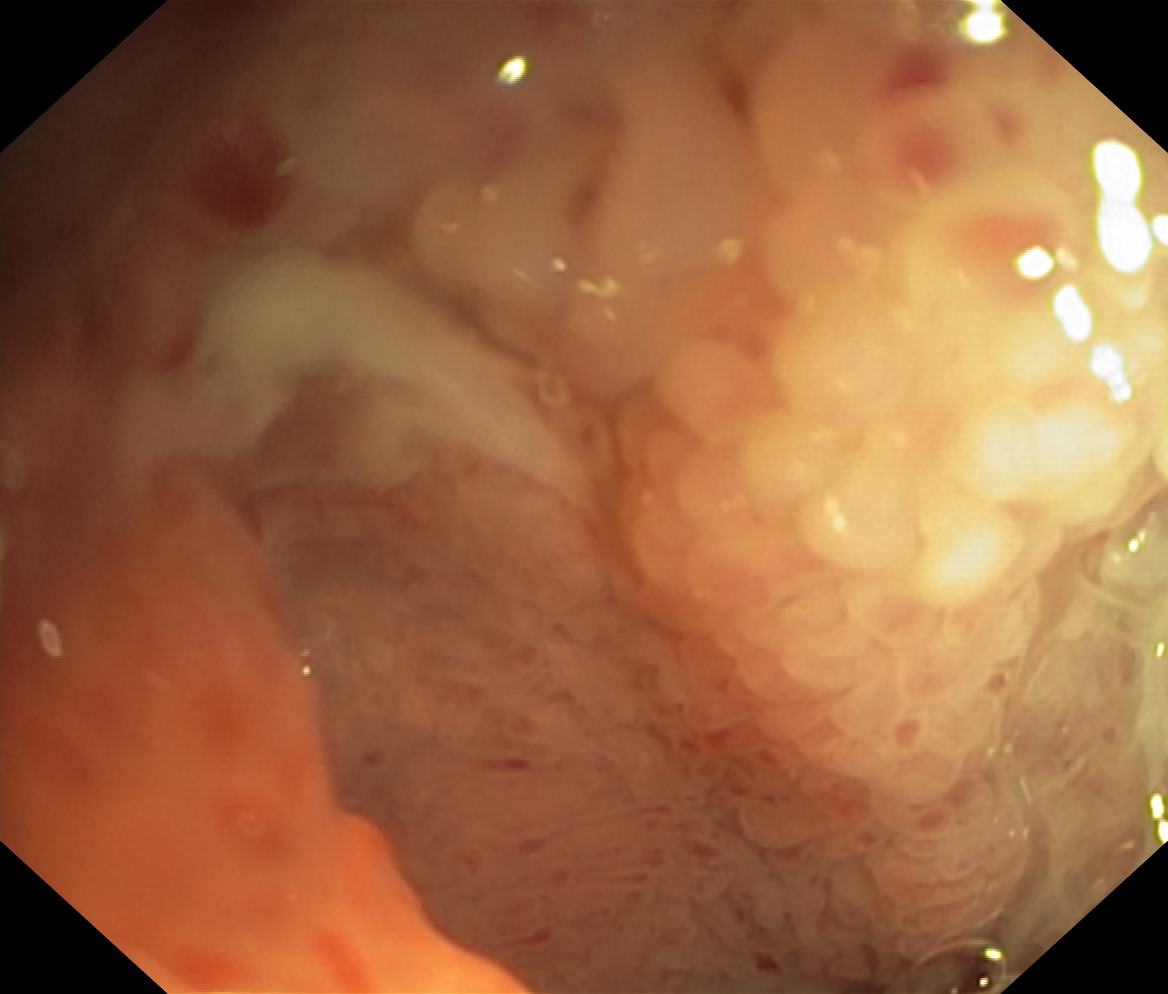

Choroba Leśniowskiego-Crohna